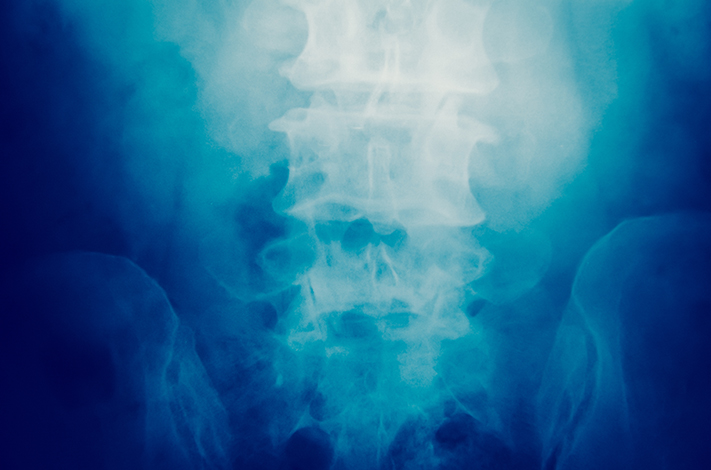

The centre for spinal surgery at Medical Trust Hospital, Kochi was established to provide therapies and treatments for patients with spinal deformities and injuries. Our spine centre incorporates expert spinal surgeons, specialists and utilizes the latest medical equipment for diagnostics and treatment. We make use of modern implants such as pedical screw system, spinal fixation systems, inter-body cages, spacers, plate, screws etc.  Our spine centre also performs all Neurospinal procedures and treatments.